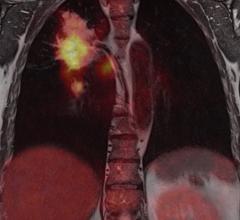

Lung Imaging

News and new technology innovations concerning how imaging technology for the lungs. This includes computed tomography (CT), X-ray and ultrasound imaging of the lungs to diagnose and monitor treatment for lung cancer, COPD, pulmonary embolism (PE), pneumonia, tuberculosis and COVID-19 can be found on this channel.